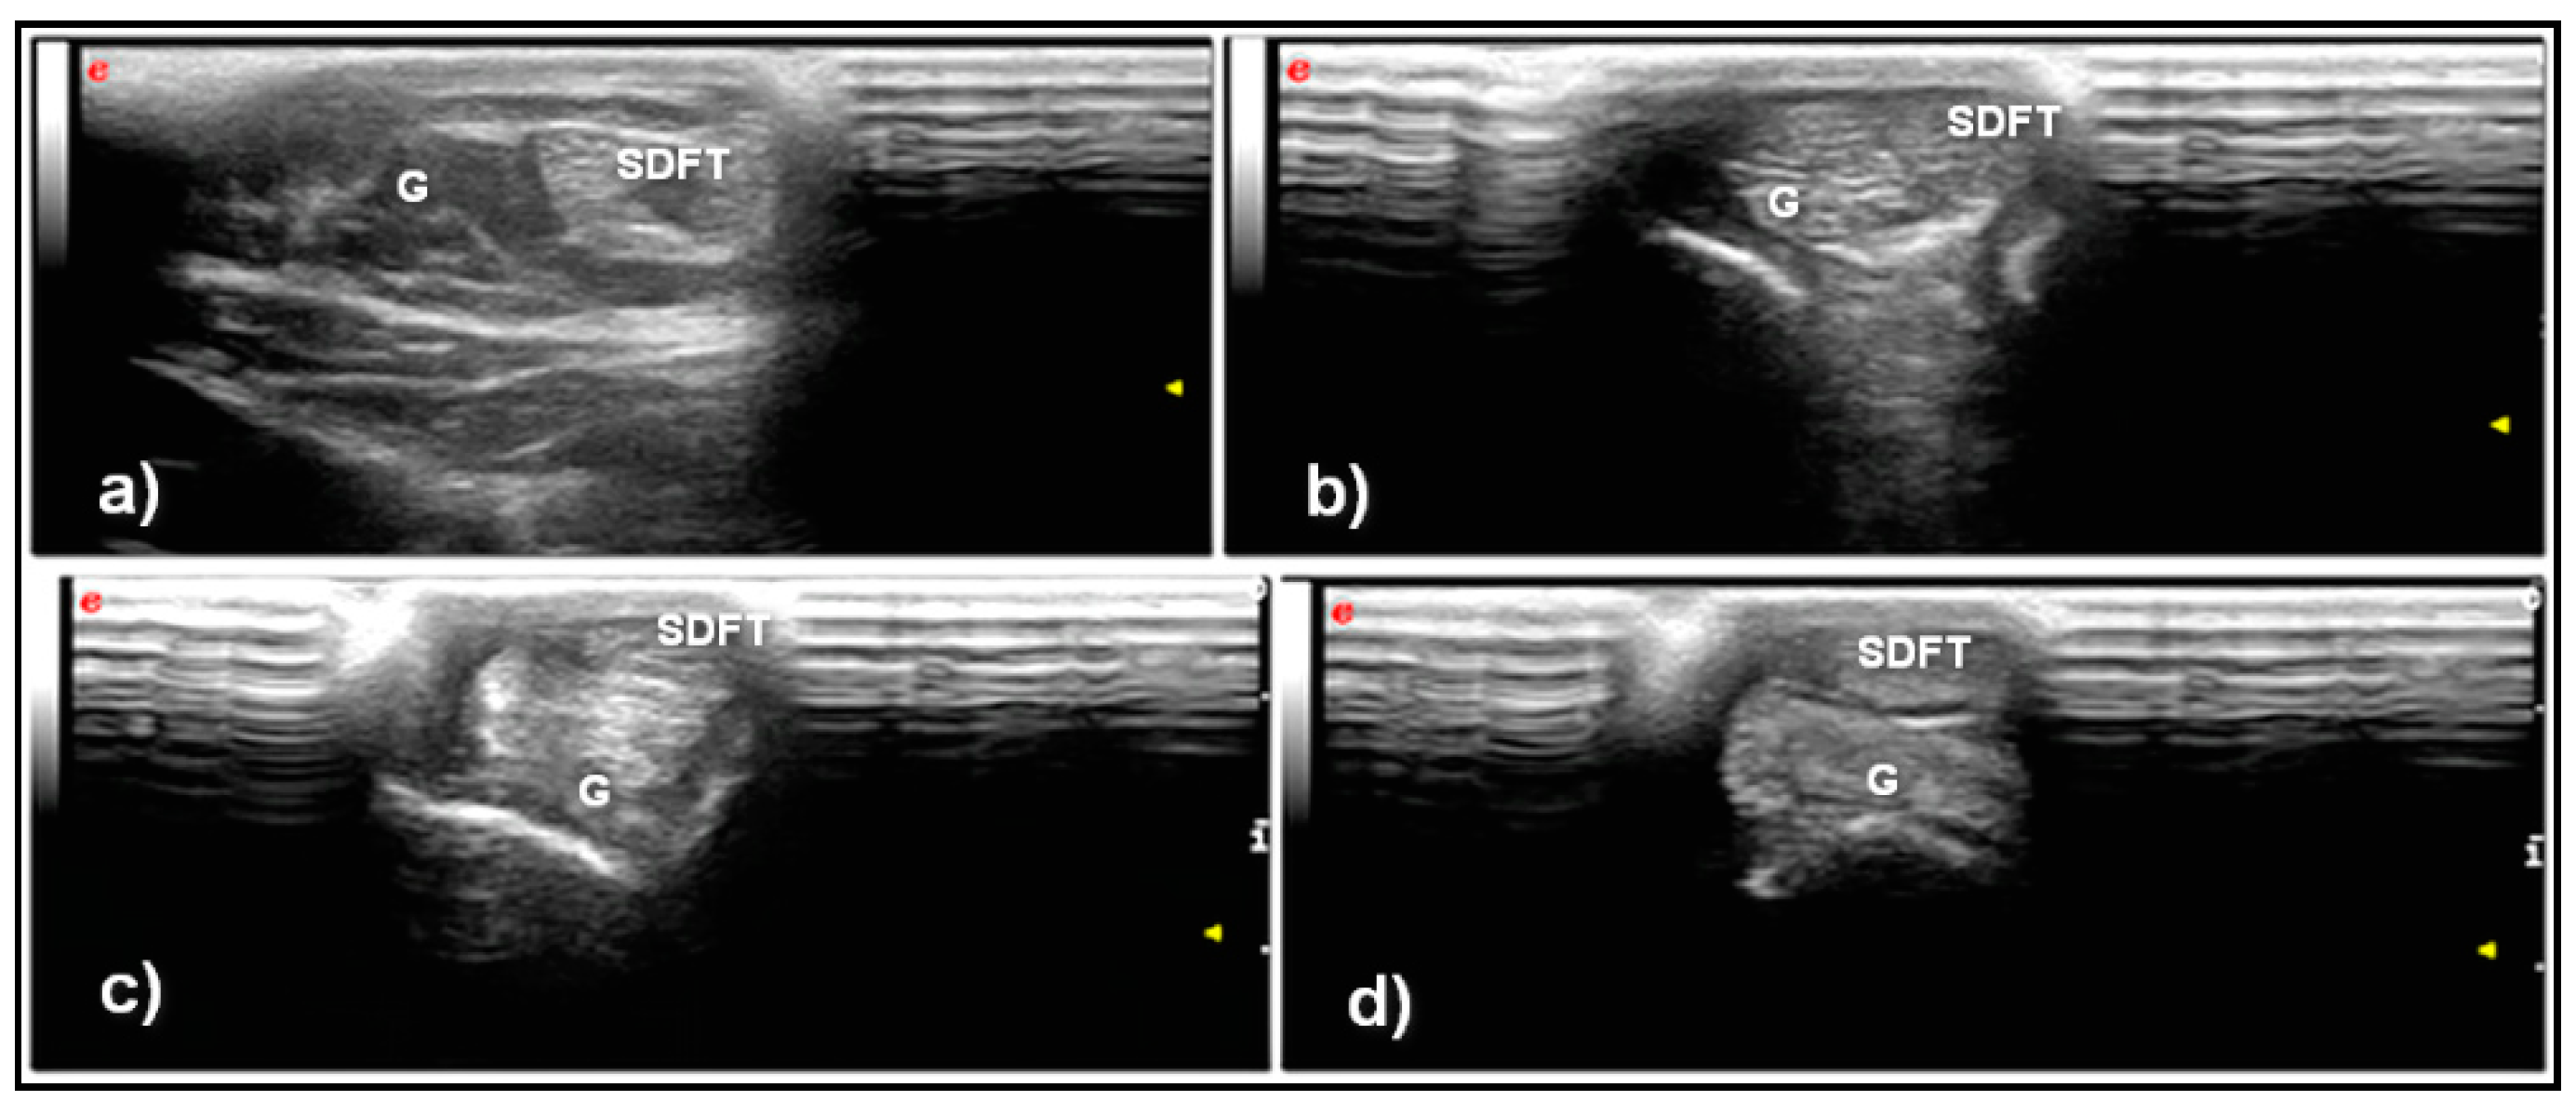

3. Results